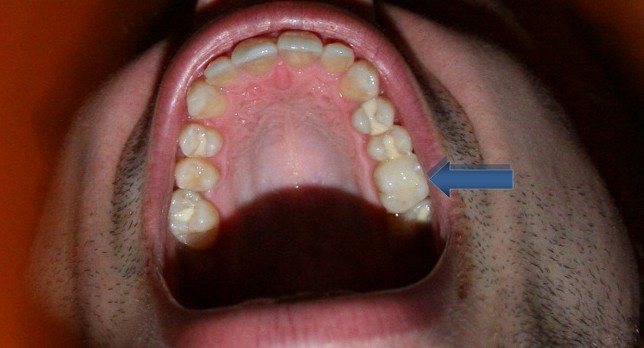

As you can see below, the man has numerous white fillings on his back teeth (this is a view of his upper teeth from below). This picture is a good example of how picking the wrong shade of white can make a filling stand out even more. Some of the fillings are easy to see because they are not matched very well to the shade of the tooth.

I have the arrow pointing at one of the more inconspicuous white fillings where the shade of filling material more closely resembles the tooth’s natural shade. If you look closely you can see that in the middle of that tooth there is a big white filling.